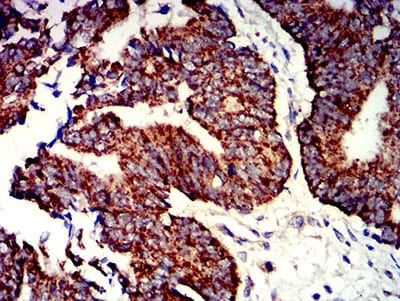

Immunohistochemical analysis of paraffin-embedded human bladder cancer tissues using P2RY1 mouse mAb with DAB staining.

Immunohistochemical analysis of paraffin-embedded human rectum cancer tissues using P2RY1 mouse mAb with DAB staining.